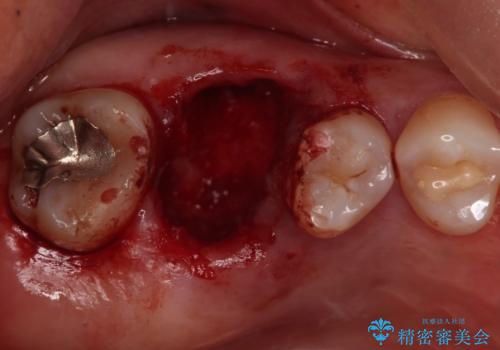

今回は抜歯後に骨の補填材を足し、適合の良いブリッジを装着していくこととなりました。

抜歯後そのままブリッジを入れるとブリッジと歯茎の間に大きなすき間ができてしまいます。その結果食べ物がつまりやすくなったり、息もれが生じたりと日常生活に支障をきたしてしまうことがあります。

抜歯後に骨を増やしてあげることで、ブリッジと歯茎との間にすき間が生じにくくなり、適合の良いブリッジを入れることが可能となります。